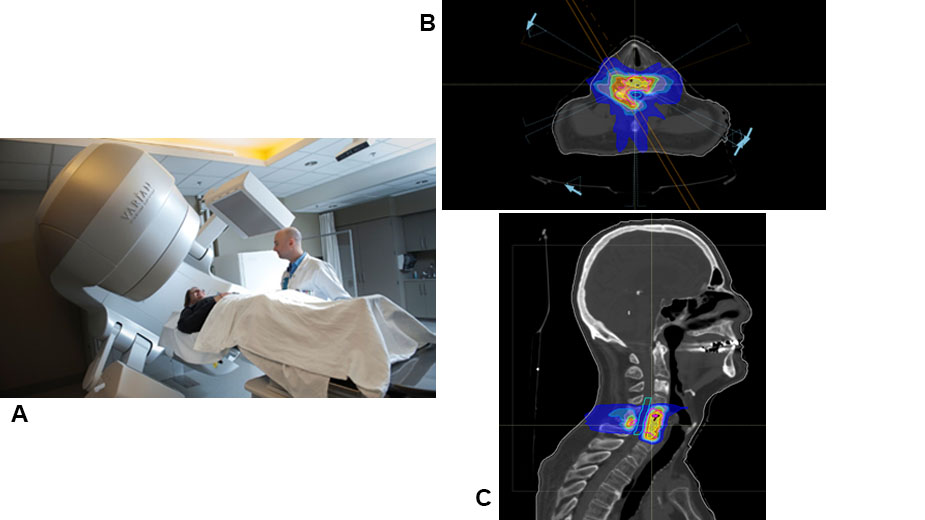

A. This patient is being positioned within the linear accelerator to receive stereotactic radio-surgery (SRS), a form of external beam radiation. B & C. Cross section and side views of the treatment plan. Each color overlay represents a specific dose of radiation to be delivered to that area.